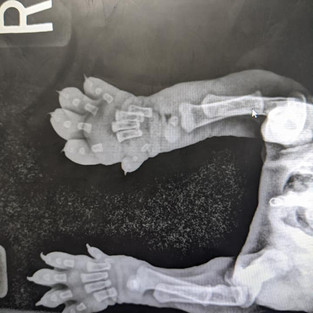

The very next day, I performed what is easily the MOST stressful surgery I have ever performed in my life. Surgery, though I am good at it, is not my favorite thing. Surgery on a 3 week old, 2.75lb, sick puppy to amputate part of his foot, was definitely not high on my to do list. Thankfully, we were able to perform it very quickly, and both Kira and Mark monitored his anesthesia and he did awesome. Kira took him home on fluids overnight, and was his 24-7 nurse for the next several days – bottle feeding him, warming him, and giving him supplemental fluids and his antibiotics, as he recovered. The first few days were a little rocky, but he hung in there and slowly started getting stronger and bigger each day. That surgery marked the start of a nearly 10 month saga with this leg.

The infection was so bad, in such a tiny body, that we had a hell of a time getting it under control. He was on and off antibiotics for the next 10 months. Many cultures, laser treatments, acupuncture treatments, and even a custom fit brace later, we just kept losing the battle with the infection that had settled in his bones. He had 2 additional surgeries with our orthopedic surgeon, Dr DeNardo, to shorten the leg and try to cut off the infection, but the wound just kept opening up. Finally in November, we admitted defeat and amputated the leg – which was surgery number four for our brave warrior.